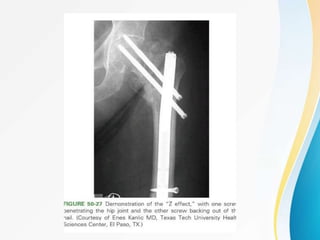

• Lateral migration of the lag screw and the

concomitant medial migration of the

antirotation screw.

• Both the screws come under cyclic loading.

• The proximal thinner screw bends easily, jams,

fails to slide and cuts off the head.

• The distal thicker screw is minimally affected

retaining its sliding properties, permits

impaction of metaphyseal fracture area.

Z EFFECT :

• Lateral migrationof the lag screw and the concomitant medial migration of the antirotation screw. • Both the screws come under cyclic loading. • The proximal thinner screw bends easily, jams, fails to slide and cuts off the head. • The distal thicker screw is minimally affected retaining its sliding properties, permits impaction of metaphyseal fracture area. Z EFFECT :